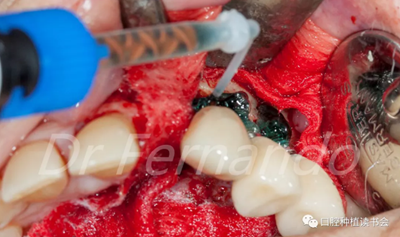

然后根據(jù)種植體周圍炎的標(biāo)準(zhǔn)治療程序,先使用磷酸&氯己定凝膠處理種植體表面2分鐘后,接著使用抗生素溶液(透明質(zhì)酸鈉哌拉西林他唑巴坦)處理5分鐘,然后使用Cerasorb ?M 骨粉植骨(Curasan?-科盧森)(圖 21)。

圖21 機(jī)械&化學(xué)凈化種植體表面后,使用Cerasorb ?M 骨粉植骨